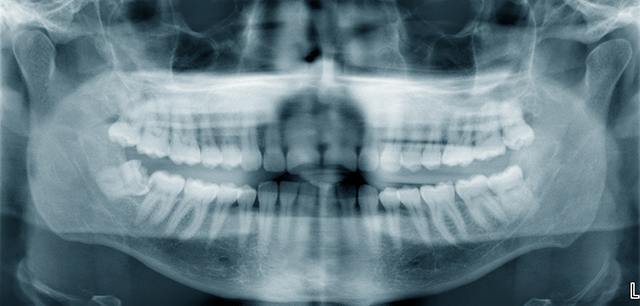

虫歯治療の第一歩は、しっかり検査し、的確な診断を行うことから始まります。吉祥寺ハイジア歯科医院では、初診の際、虫歯や歯周病に対して検査とその結果に十分な時間をかけています。